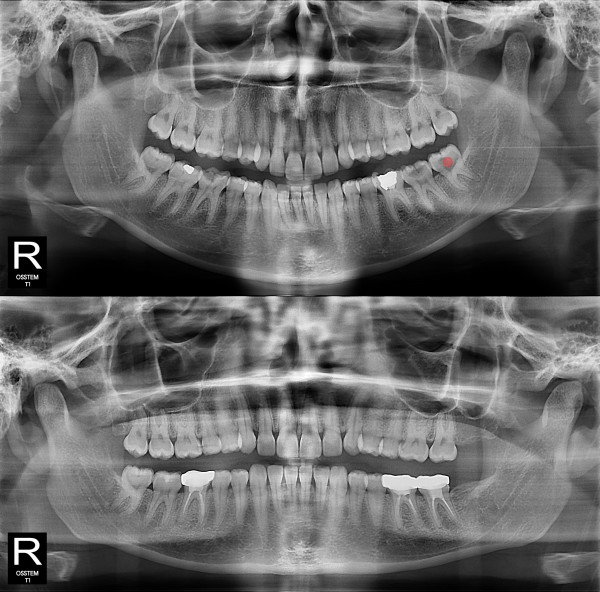

智齿拔除 严重龋坏的智齿